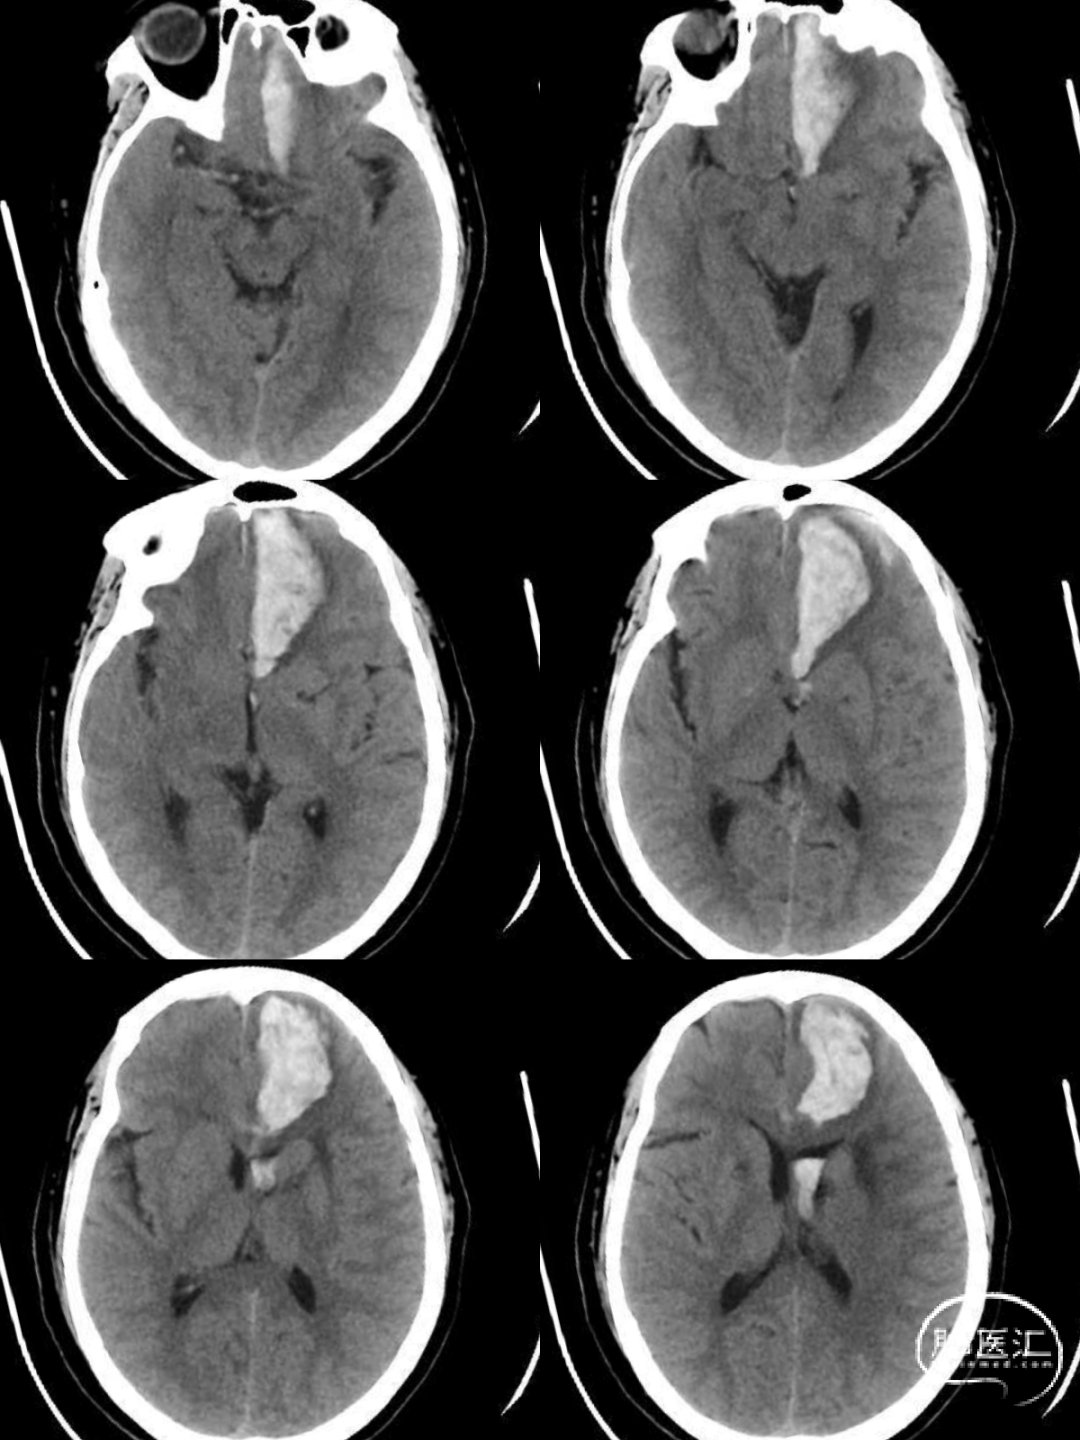

头颅CT:左侧额叶脑出血伴血肿形成,破入脑室系统,请结合临床,建议复查(图1)。

图1 急诊CT平扫